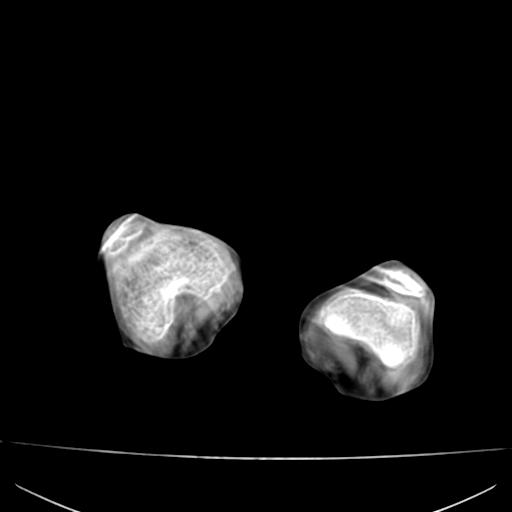

标题: PED0940:M12Y,左股骨下端酸痛畸形 [打印本页]

标题: PED0940:M12Y,左股骨下端酸痛畸形

12岁男孩,左膝关节肿痛8年,近月明显

内生骨软骨瘤?

血友性关节病?